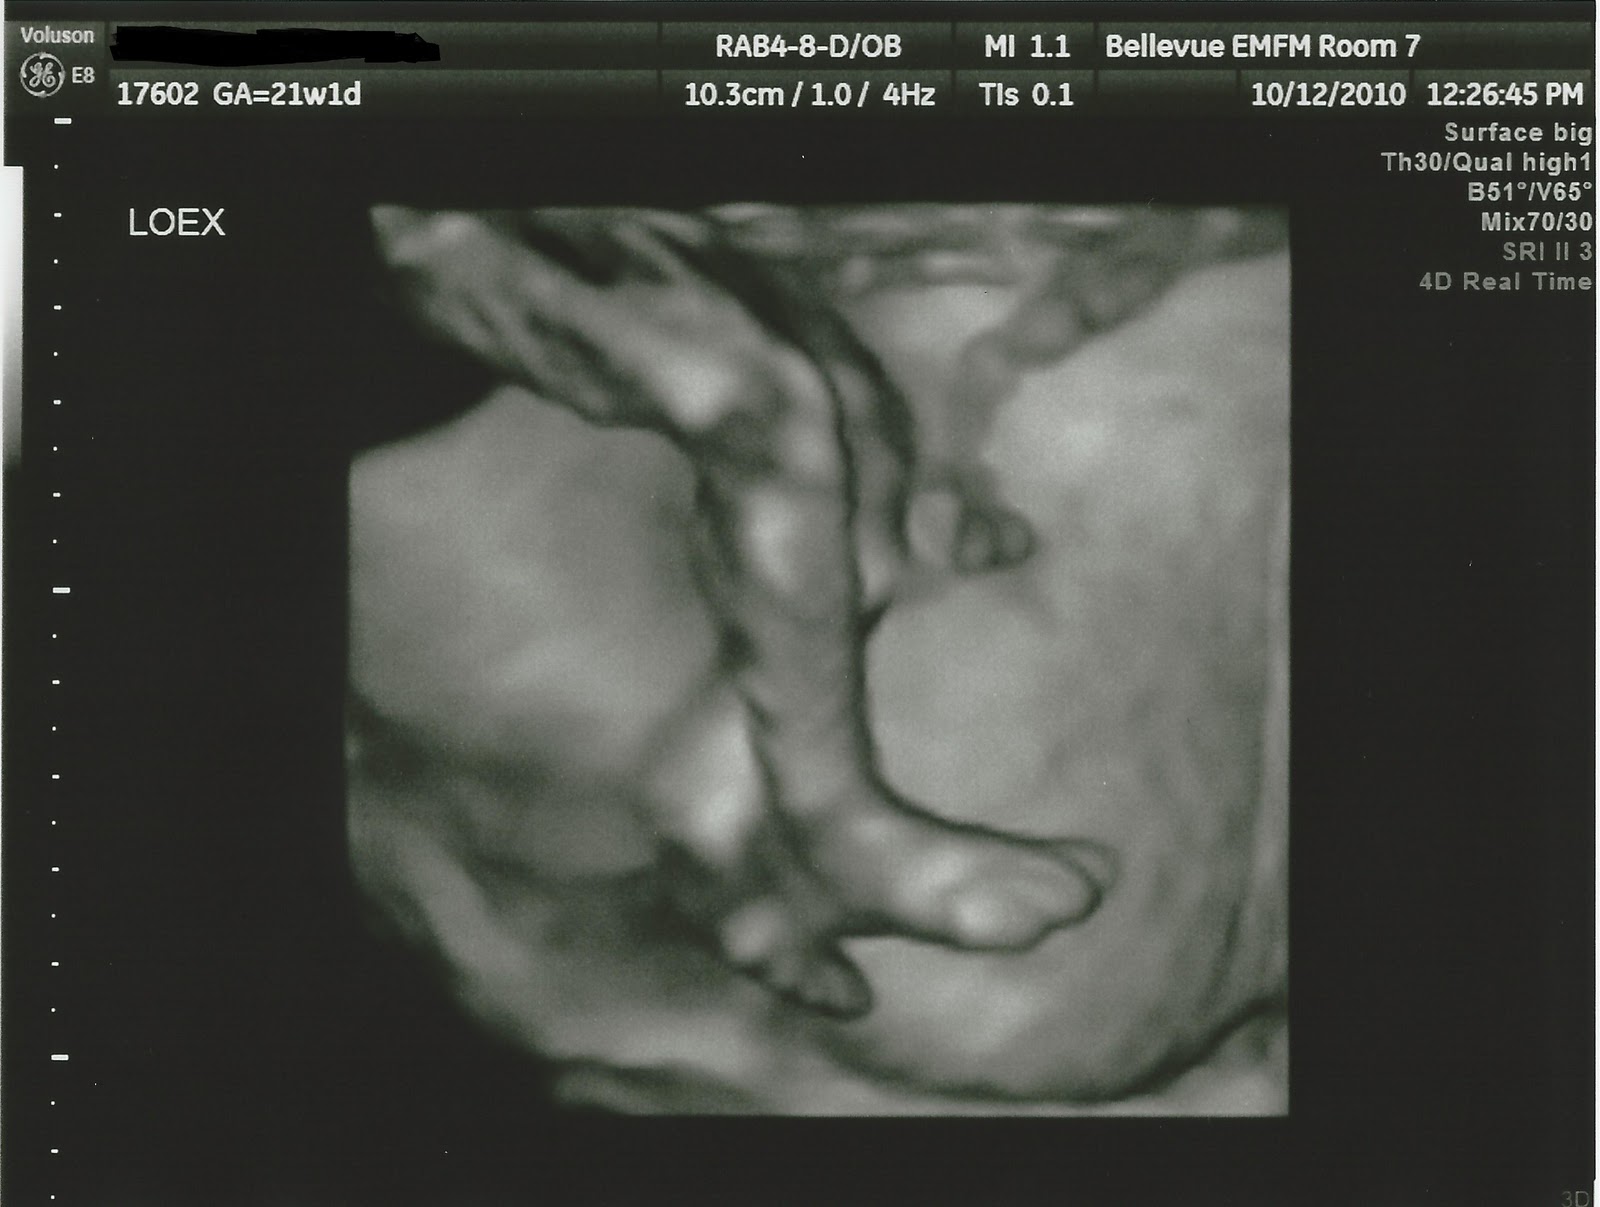

Pictures of our Walnut from the 20 week ultrasound